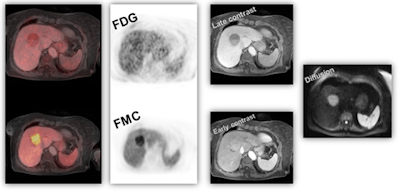

Figure 1: Dual tracer, multiparametric PET/MRI using F-18 FDG and F-18 FMC for noninvasive tumor characterization in a 70-year-old patient with suspected hepatocellular carcinoma (based on EORTC-criteria) prior to resection. Image courtesy of Dr. Markus Hartenbach, Medical University Vienna in Austria.It was with the physical combination of noninvasive imaging methods, such as SPECT/CT, PET/CT or, lately, PET/MRI that for the first time cross-specialty thinking sunk into the minds of the diagnostic clinical experts, and following clinical implementation, gave rise to documented evidence of increasing diagnostic accuracy.1,2 However, when presenting that imaging information in clinical tumor boards, or alike, it became clear that effective patient management mandates additional information that include pathology and data analysis methods.3 These fields, while being in active pursuit by several groups, could not be regarded independently any more, particularly when addressing severe illnesses, such as cancer or other metabolic diseases.

Conjoined assessment of morphology, metabolism, and pathology becomes even more important when assessing therapy response4 when lesions may respond biologically but no alteration of the morphology is detected (figure 2). To date, numerous novel and effective pharmaceuticals for therapeutic interventions are available. If chosen wisely, these therapies can be efficient.5 However, frequently an a priori patient selection for the most appropriate therapy is missing, mainly due to missing out on molecular imaging information. Therefore, antitumor therapies may lack efficiency.6

Figure 2: Patient with gastrointestinal stromal tumor (GIST), showing early metabolic response to Imatinib therapy (F-18 FDG PET, left side), without change in size of the tumor (CT, right side). Panels modified from (4).Although continuous scientific improvements are being made and new therapeutic options become available, equally relevant improvements in outcome measures (e.g., overall survival, time to tumor progression, patients' well-being) are rarely observed. On the contrary, the economic burden for the healthcare systems increases steadily, both on an overall and an individual scale without matching benefit for the treated patients7 (figure 3).